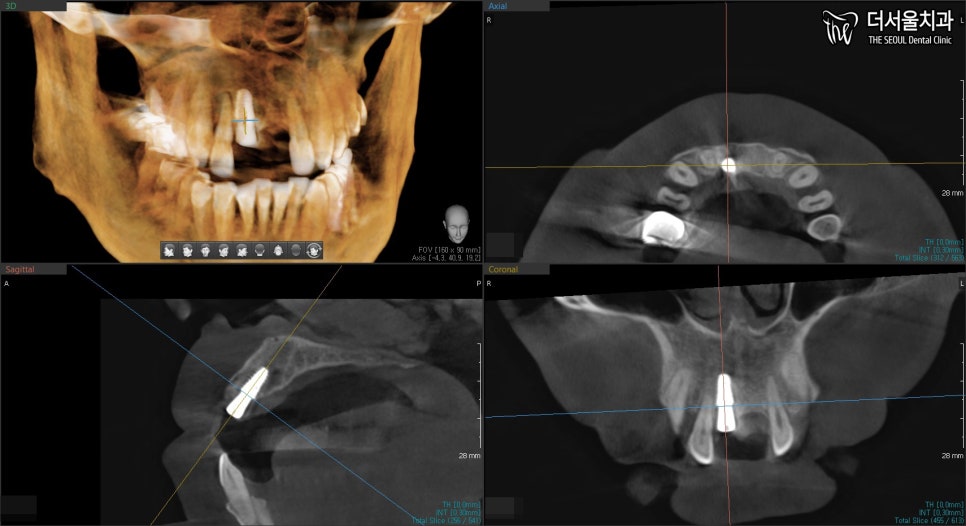

3. 계획 짜기

현충일 공휴일 정상진료

3D 디지털 프로그램을 이용하면,

모의 수술을 해볼 수 있습니다.

디지털로 스캔 뜬 모형을 기준으로

뿌리인 픽스처를 어떻게 심으면 될지,

그 위에 어버트먼트와 크라운은

어떤 형태로 만들어 연결시키면 좋을지 말이죠.

또, 이런 식으로 여러 각으로

심어놓은 결과물을 볼 수 있습니다.

이렇게 데이터를 만들어 놓고 나면

서현역 치과는 수술에 들어갑니다.